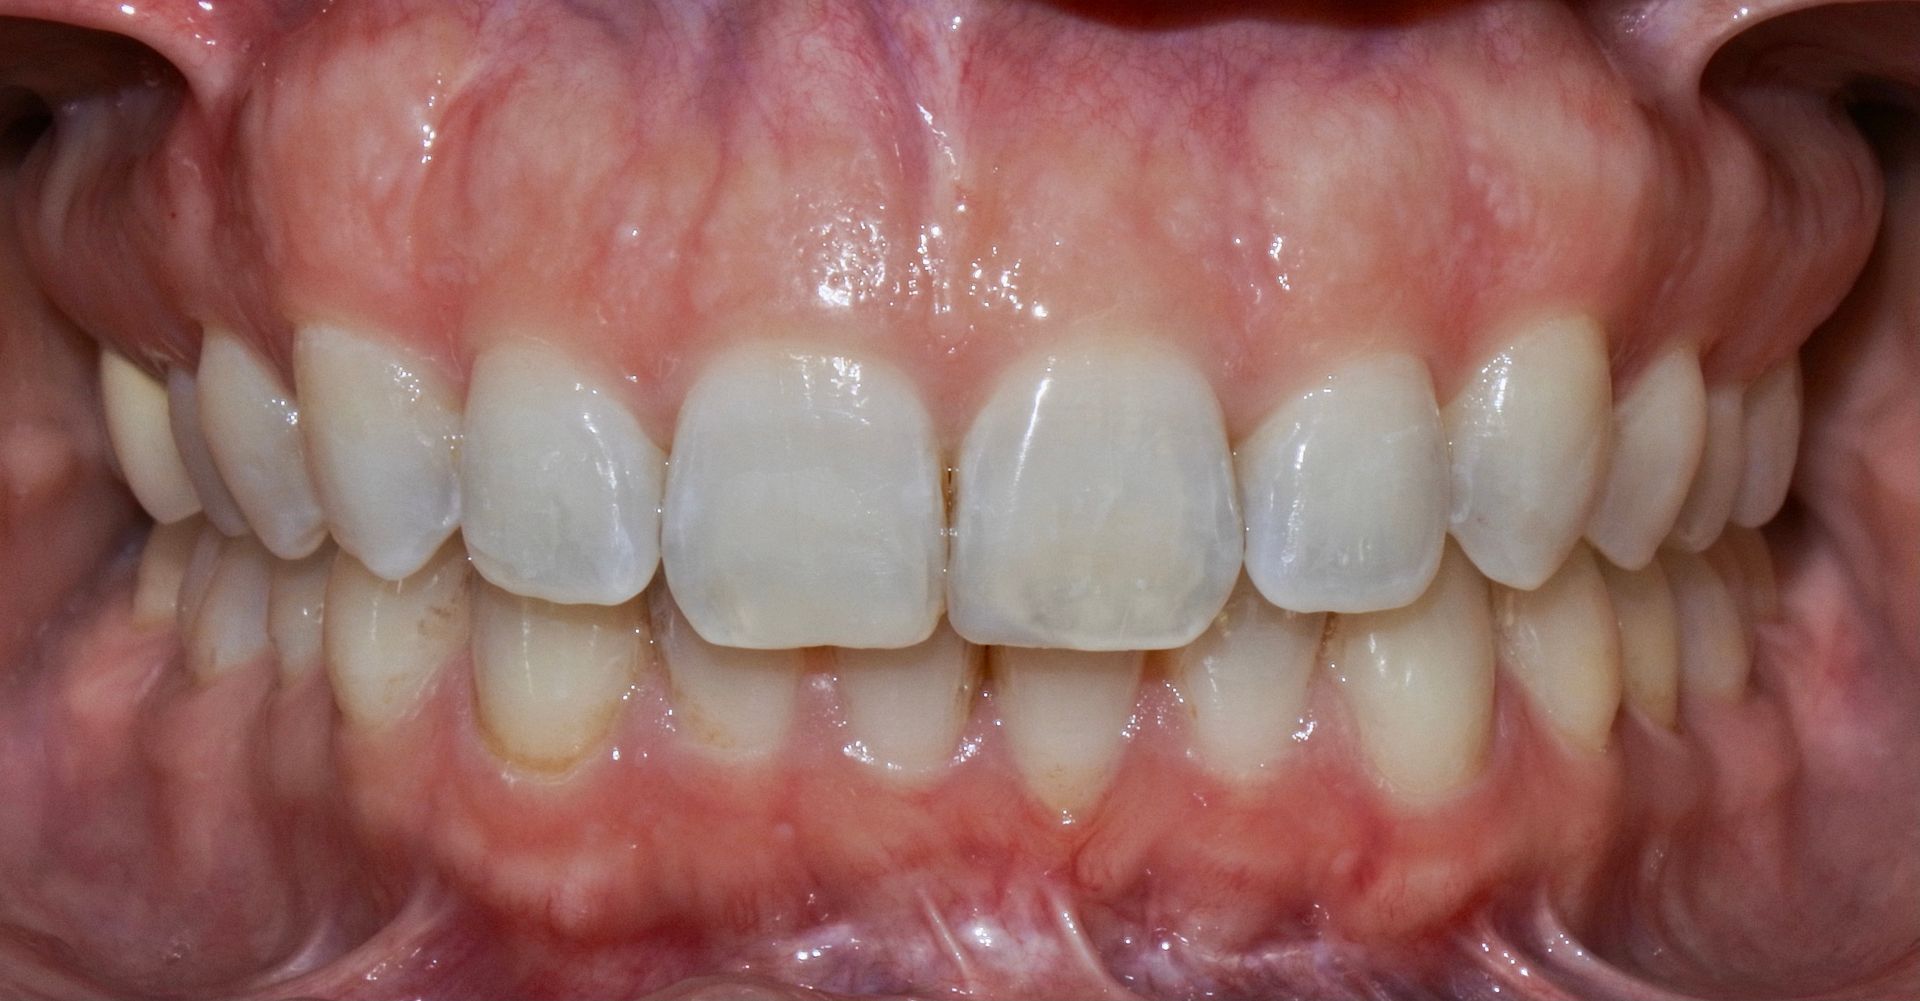

Le mascherine personalizzate, praticamente invisibili, vanno indossate dal paziente 20/22 h al giorno, consentendo così di poter mangiare e lavare i denti senza problemi.

Questo è l'enorme vantaggio rispetto all'ortodonzia tradizionale, dove i brackets (attacchi) sono fissi sui denti.